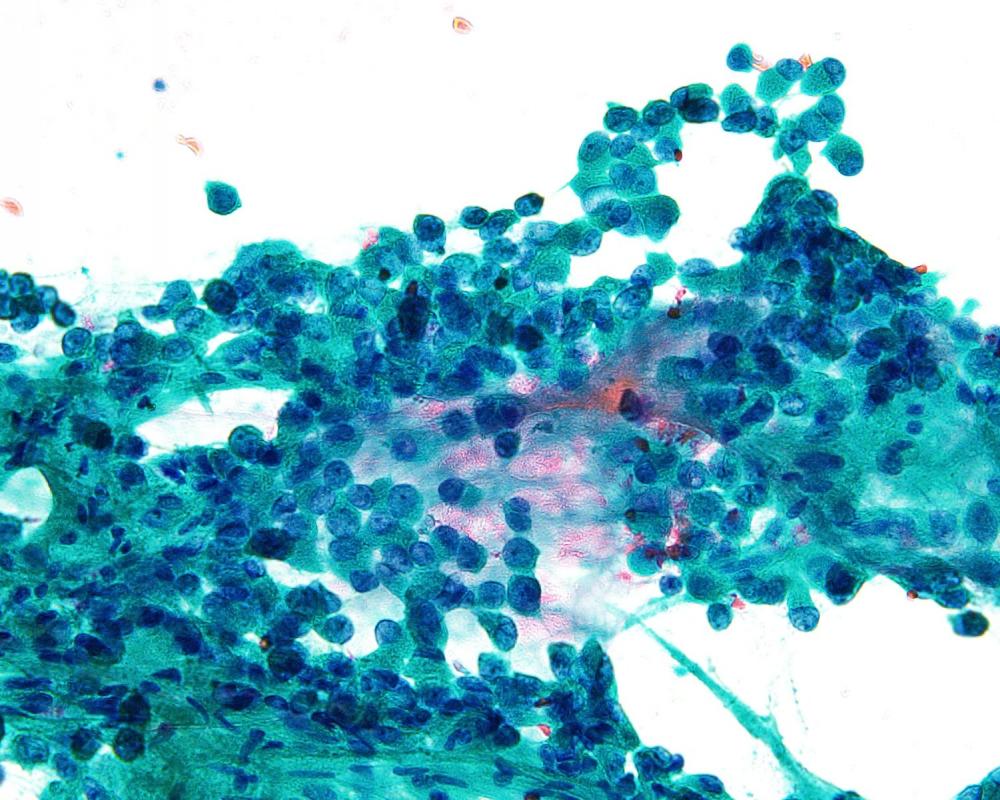

第40回日本臨床細胞学会九州連合会学会(大分)スライドカンファレンス症例2

種別:呼吸器

出題:今村 彰吾 独立行政法人国立病院機構九州がんセンター

| 年齢 | 50歳代 | 性別 | 女性 |

| 採取部位 | 気管支 | 採取方法 | 気管支鏡下生検捺印 |

既往歴 右頬粘膜癌(7年前)および肺転移(8年前)、歯肉癌(2か月前)

現病歴 右頬粘膜癌に対してニボルマブ投与中、PET-CTにて左気管支内に異常集積を指摘され、精査目的で当科紹介受診となった。

| 正解 | 5.間葉系腫瘍 |

▼選択肢及び投票結果

| 1.扁平上皮化生細胞 | 4件 | (3.8%) | |

| 2.扁平上皮癌 | 6件 | (5.7%) | |

| 3.腺癌 | 0件 | (0.0%) | |

| 4.非小細胞癌(肉腫様癌) | 35件 | (33.3%) | |

| 5.間葉系腫瘍 | 60件 | (57.1%) | |

| 投票総数 | 105件 | (100%) |